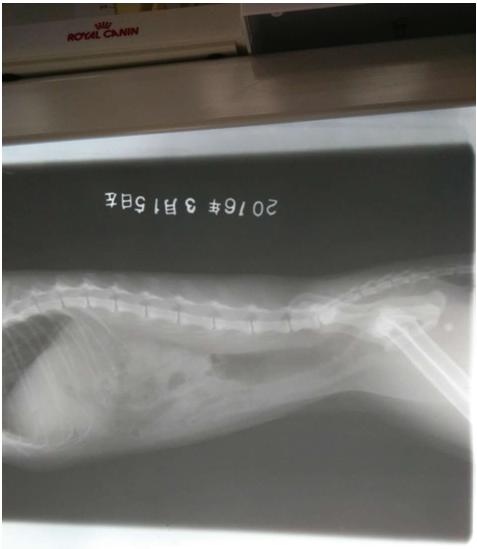

猫加肥,6m,雌性。最近小便带血,遂来院就诊。

从临床表现的主要症状,结合辅助检查结果初步诊断为出血性膀胱炎并结晶尿。

3、在条件允许的情况下,应定期对患猫做X射线、B超复查, 以便了解该病的预后状况,若出现异常情况要及时做出适当的处理。